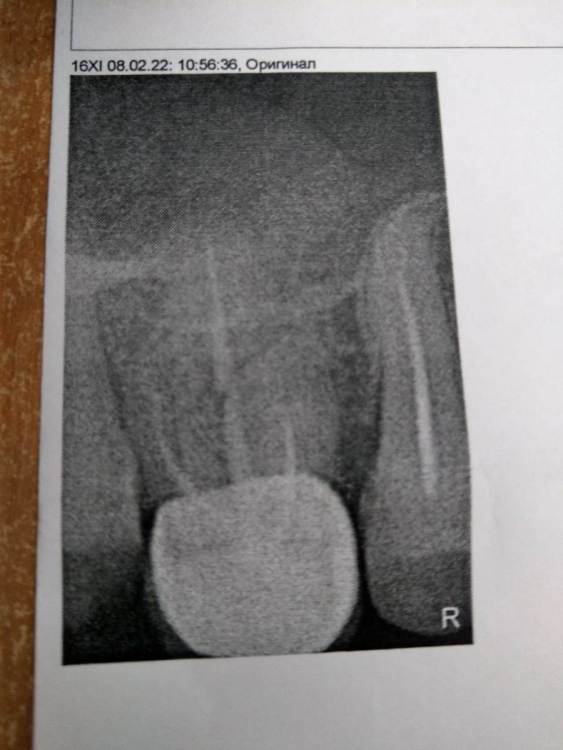

Алексей82 Опубликовано 9 февраля, 2022 Поделиться Опубликовано 9 февраля, 2022 Здравствуйте. Подскажите пожалуйста надо ли чистить правый канал? Врач говорит что он чуть не до чищен, но гарантий что будет лучше или хуже никто не даёт. Зуб не беспокоит. Коронки пломба стоит больше 10 лет. Сейчас надо поменять корону, т. к. снизу ставлю имплант, а верхняя коронка выдвинулась. Доктор говорит, когда будет стоять имплант возрастёт нагрузка на верхний зуб и могут быть неприятности, а может и не быть. За чистку каналов тоже говорят, что возможна перфорация или это в трудно доступный канал - принимай решение сам. Стоит ли туда лезть? Ссылка на комментарий

wladdX Опубликовано 10 марта, 2022 Поделиться Опубликовано 10 марта, 2022 (изменено) Попробовать поработать в корневых каналах можно, насколько это будет успешно, сказать невозможно. Изменено 10 марта, 2022 пользователем wladdX 1 1 Ссылка на комментарий